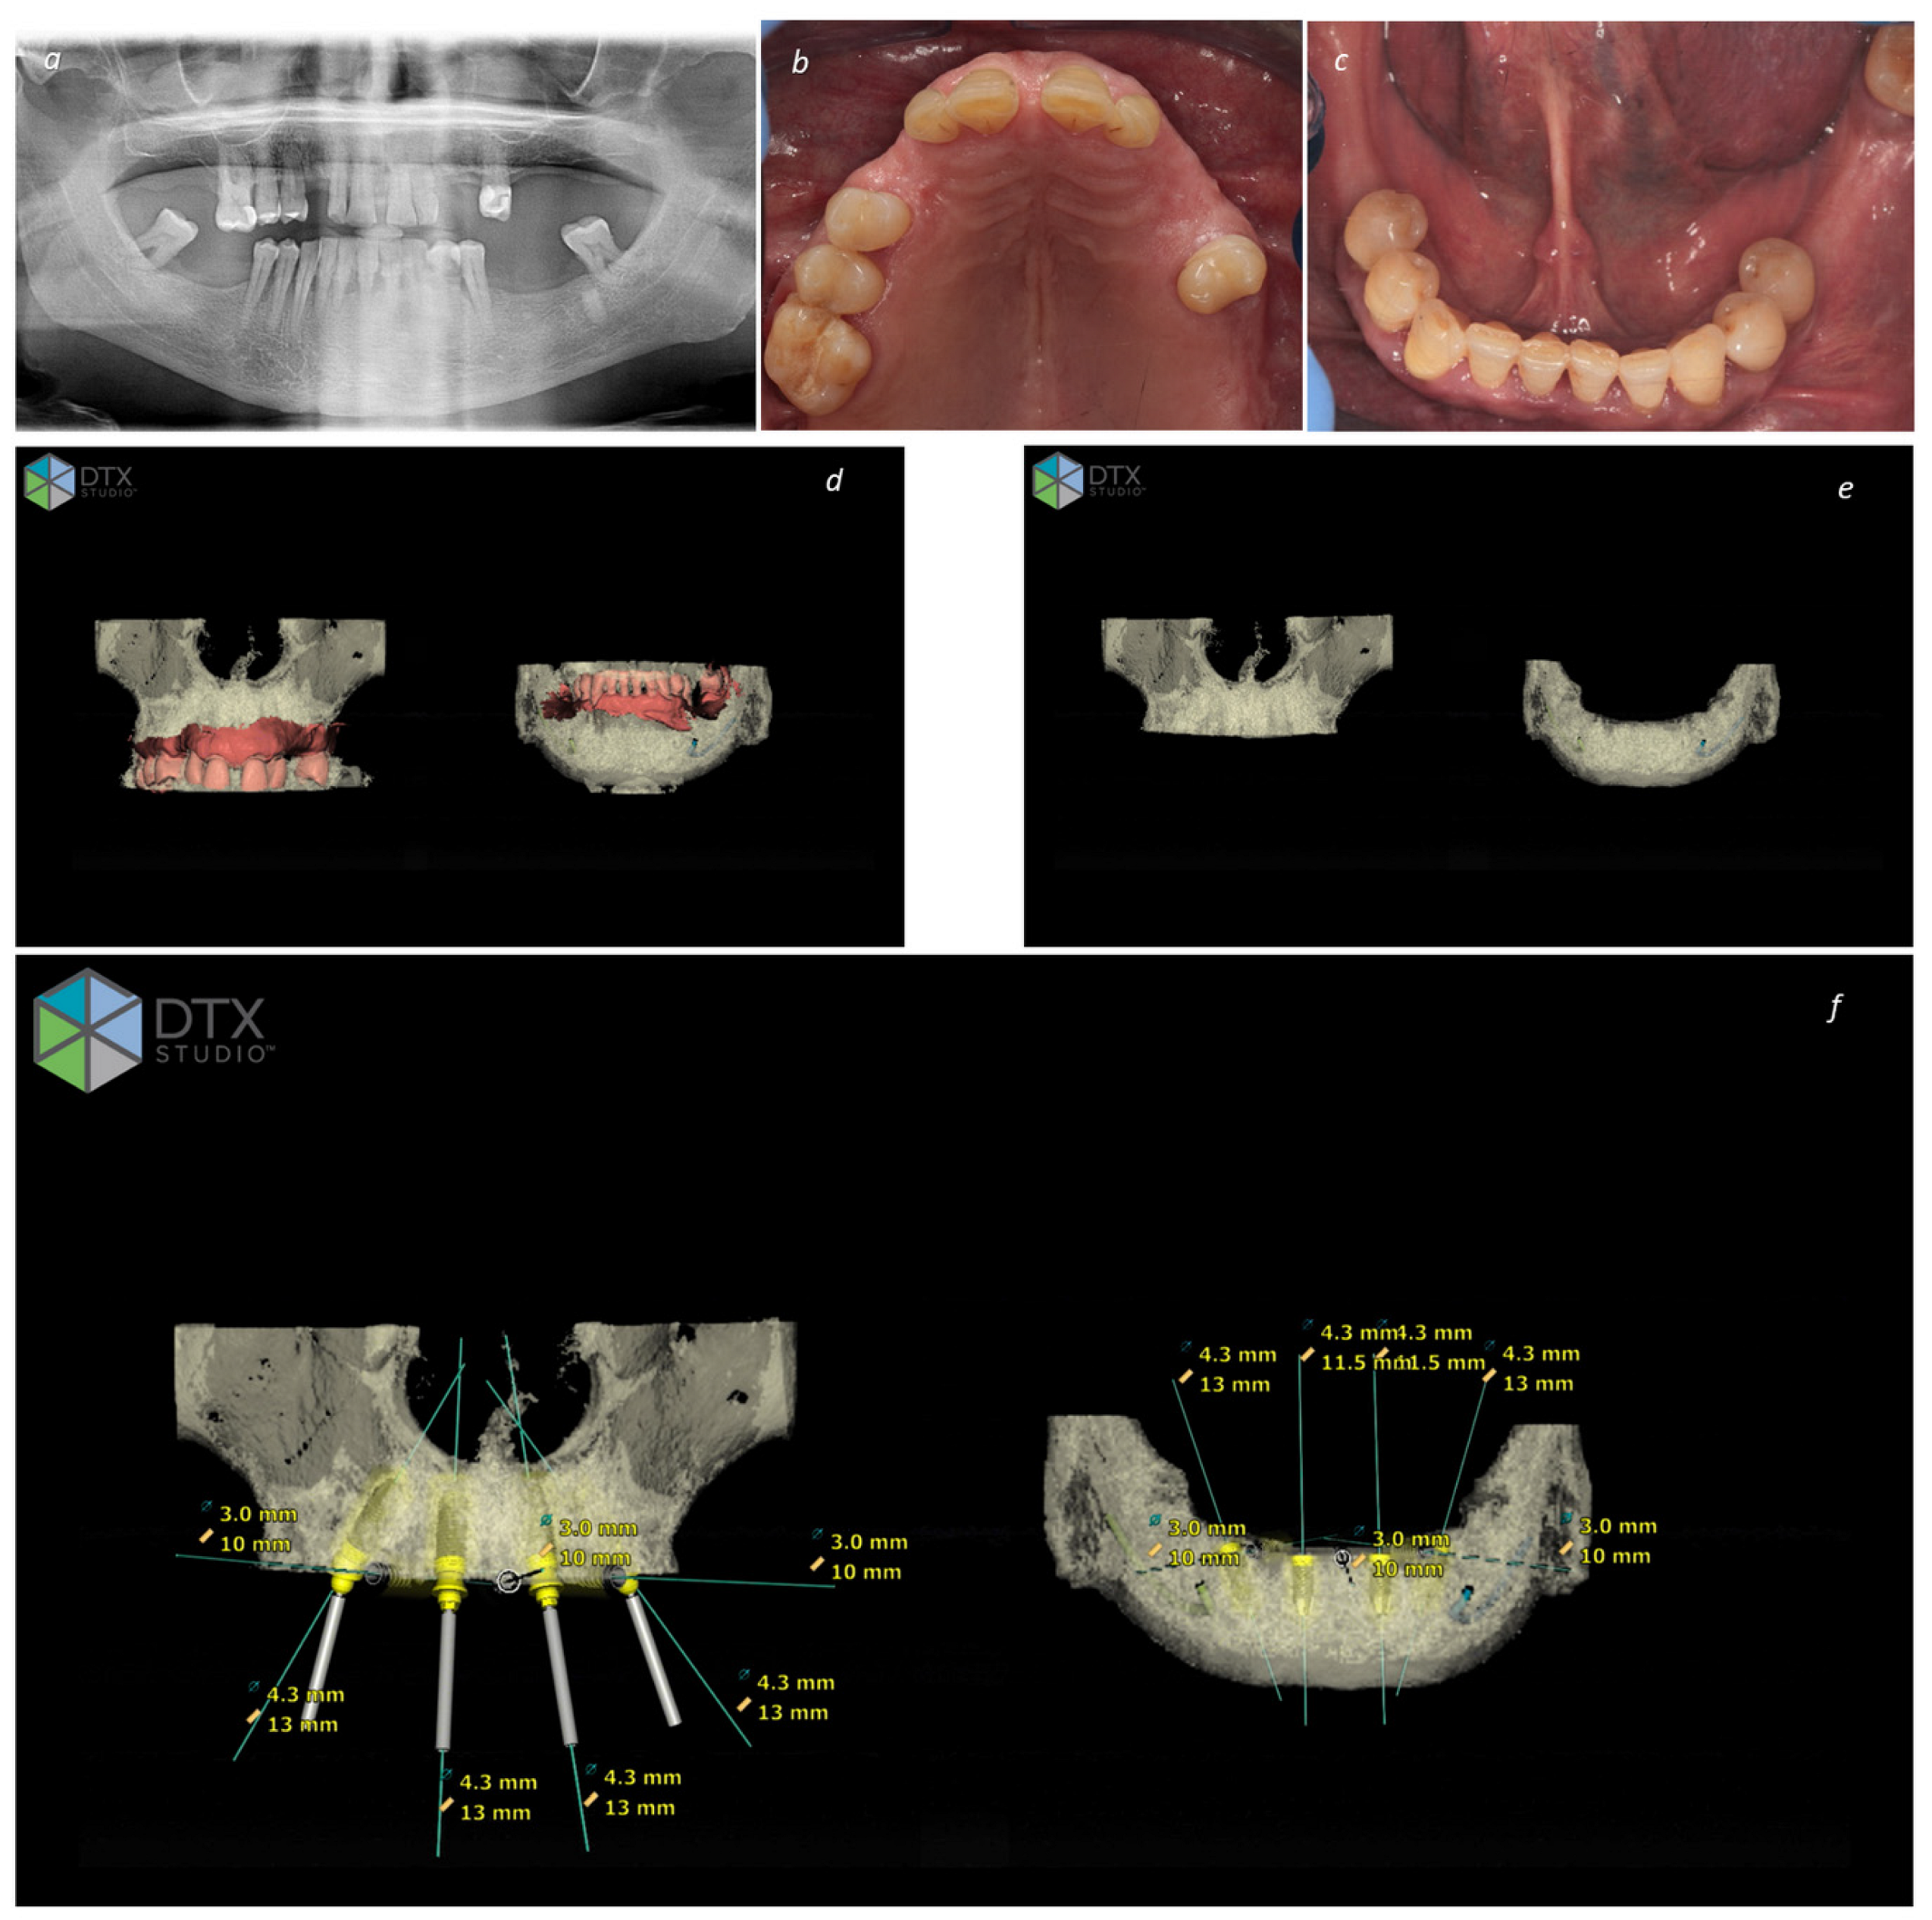

Figure 1.

Planning a full-arch bimaxillary rehabilitation through the All-on-4 Concept: (a) Pre-treatment orthopantomography; (b) Pre-treatment intraoral photograph of the maxilla; (c) pre-treatment intraoral photograph of the mandible; (d) DTX Studio image exhibiting the pre-treatment condition in the maxilla and mandible with superimposition of CBCT and Intraoral Scanner (smart fusion); (e) DTX Studio image of the planning exhibiting the bone regularization to achieve a stable platform for implant insertion in the maxilla and mandible; (f) DTX Studio image of the final planning exhibiting the implant planning (diameter and length) in the maxilla and mandible.